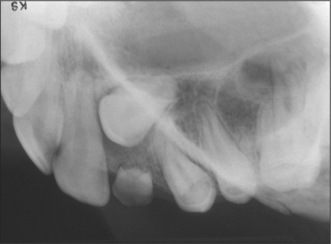

4. The patient in Fig. 12.19 presents with a pronounced labial fraenum and a median diastema.

(a) How else might the extent of the fraenum be visualized?

(b) What are the indications for lingual fraenectomy?

image

Fig. 12.19 See question 4.